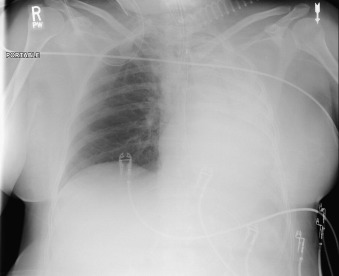

Complications of intubation ( Figs. 25-1 to 25-10 ) and ventilation that are apparent on a chest radiograph are often potentially life-threatening and should be excluded on every radiograph, both immediately following intubation and with each subsequent radiograph. These possibilities are listed in the following sections.

Esophageal Intubation

Distension of esophagus and stomach with air

Location of ET tube to the side of the trachea

Cuff Overinflation

The walls of the trachea should not be distended outward by the cuff. Distension is overinflation.

Width of the ET tube two thirds of the width of the trachea